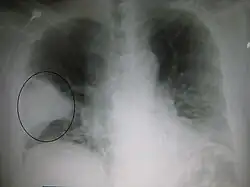

Et røntgenbillede der viser en fremtrædende kileformet bakteriel pneumoni i højre lunge. | |

De fleste bakterier når lungerne/svælget ved indånding af små mængder organismer fra hals eller næse.[11] Halvdelen af alle normaltfungerende mennesker indånder små mængder væske/stof til lungerne, når de sover.[18] Der findes altid bakterier i halsen, men mulige smittebærere er der kun på bestemte tider og under bestemte forhold.[18] Et fåtal af disse bakterier, såsom Mycobacterium tuberculosis og Legionella pneumophila når lungerne via kontaminerede, luftbårne dråber.[11] Bakterier kan også spredes med blodet.[12] Når først bakterierne er i lungerne, kan de invadere mellemrummene mellem celler og mellem alveoler, hvor makrofagerne and neutrofile (defensive hvide blodlegemer) prøver at gøre bakterierne inaktive.[33] Neutrofilerne udskiller også cytokiner, som aktiverer immunforsvaret.[34] Dette giver feber, kulderystelser og træthed, som er så velkendt ved bakteriel lungebetændelse.[34] Neutrofiler, bakterier og væske fra de omgivende blodbaner fylder alveolerne, hvilket kan ses på røntgenbilleder af thorax (brystkassen).[35]

Billeder

Et røntgenbillede af thorax (brystkassen) bruges ofte til diagnoser.[10] Patienter med milde tilfælde skal kun røntgenfotograferes, hvis der er mulighed for komplikationer, eller patienten ikke har reageret på behandlingen, eller hvis årsagen er ukendt.[10][38] Hvis patienten er så syg, at man må indlægge, anbefales det at tage røntgenbilleder.[38] Billedet viser ikke altid sygdommens sværhedsgrad og kan ikke skelne mellem bakterie- og virusinfektion.[10]

Røntgenbilleder af lungebetændelse kan vise lobær pneumoni, bronkopneumoni (også kendt som betændelse i en lungeklap eller pletvis udbredt lungebetændelse) og interstitiel pneumoni.[41] Bakteriel lungebetændelse erhvervet uden for sygehus viser sig typisk ved lungekonsolidering af et lungesegment, og det kaldes lobær eller primær pneumoni.[20] Men andre mønstre kan vise sig ved andre typer lungebetændelse. Ved aspirationspneumoni kan der være uklare områder nederst i begge lunger og i højre side.[20][20] Hvis lungebetændelsen er viral, kan røntgenbilleder se normale ud, eller de kan vise hyperinflation, pletter i begge sider eller de kan ligne billeder af bakterielle lungebetændelser med lungekonsolidering.[20] Røntgenbilleder viser måske ikke noget tidligt i forløbet, især, hvis patienten er dehydreret, eller de kan være svære at tyde, hvis patienten er overvægtig eller tidligere har haft lungesygdomme.[11] En CT-skanning kan give yderligere oplysninger, hvis det kræves.[20]